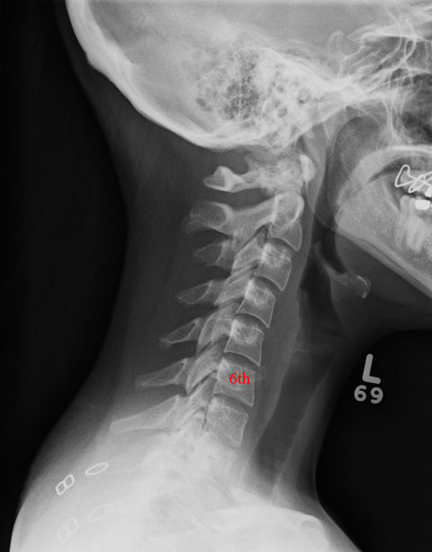

We begin by examining M2 neck wounds. They are described by Dr. Phillips as in part as,"The throat had been severed. The incisions of the skin indicated that they had been made from the left side of the neck on a line with the angle of the jaw, carried entirely round and again in front of the neck, and ending at a point about midway between the jaw and the sternum or breast bone on the right hand. There were two distinct clean cuts on the body of the vertebrae on the left side of the spine. They were parallel to each other, and separated by about half an inch. The muscular structures between the side processes of bone of the vertebrae had an appearance as if an attempt had been made to separate the bones of the neck."

When diagrammed it becomes clear that this describes a unidirectional wound type with the axis of damage running from the top left of the diagram to the vertebral body. Phillips describes hard tissue damage that indicates (to his mind) an attempt at severance of the head from the torso. Dave